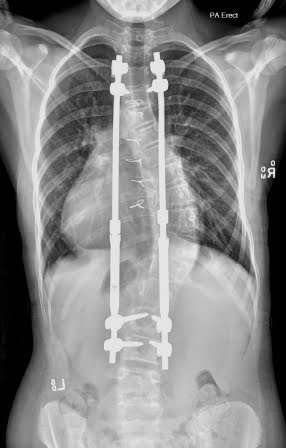

Scoliosis Treatments

Growing Rods Lengthening Surgery

About This Treatment

The lengthening procedures usually occur every six months as your child grows. The lengthenings are performed mostly as a day procedure and occasionally require an overnight stay. It is expected that the lengthening procedure should not disrupt your child to any great extent. Growing rod lengthenings will cease when the surgeon advises it is time for the permanent correction and fusion surgery.